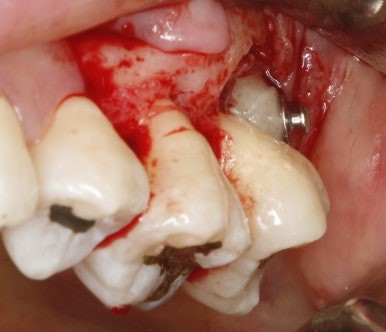

수술을 통해 장치를 위치시키고 열심히 구강내로 당겨내고 있다.